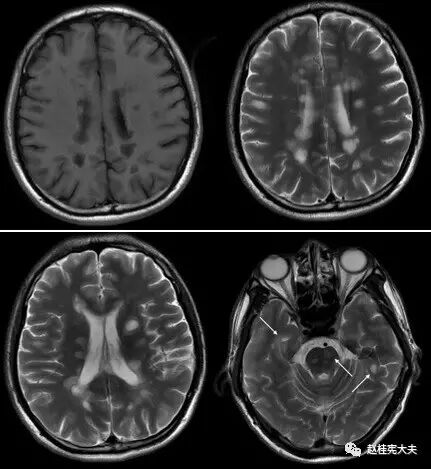

图1. 示双侧脑室旁、额、顶、颞叶皮层及皮层下,脑桥多发圆形或卵圆形病灶。T1低信号,T2高信号。

图2. 示双侧桥臂、延髓、小脑多发圆形或卵圆形病灶,T2高信号。